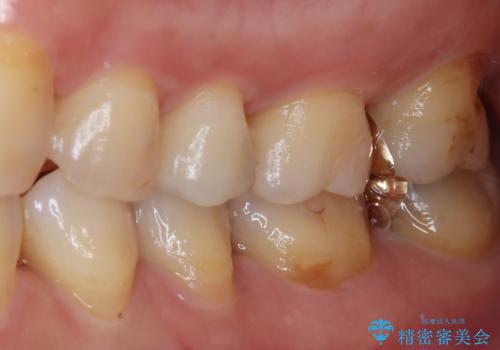

ゴールドは「白い歯」ではありませんが、銀歯の金属色とは異なり、非常にきれいな色合いが特徴です。

もちろん、適合が極めて良いという圧倒的メリットもゴールドクラウンやゴールドインレーの特徴です。